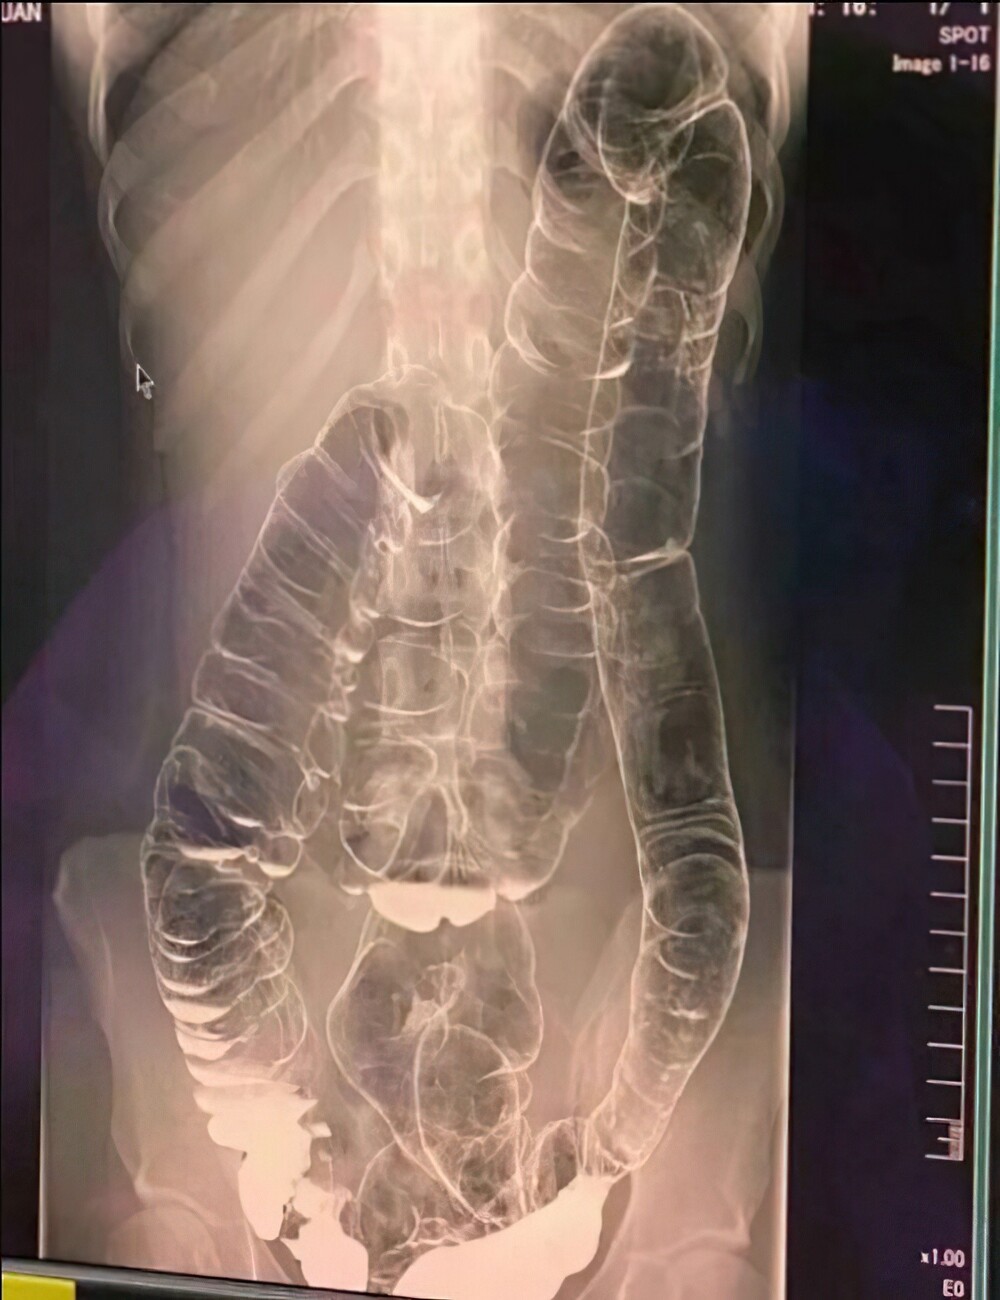

12. This is what constipation looks like after 19 days. Oh shit!

This is an image of a double contrast barium enema.